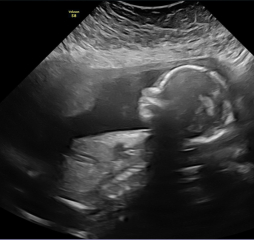

Had a private scan to see baby girl today as ive been so anxious! Everything was perfect and they did a small glampse of 4D! Look at her little fingers😍i feel like i can start to enjoy my pregnancy now that i know everything is okay!

Due March 2023 - thread 4

TeddyBeans · 18/10/2022 18:54

Katlouise24 · 18/10/2022 18:48

Beautiful pictures! 😍😍